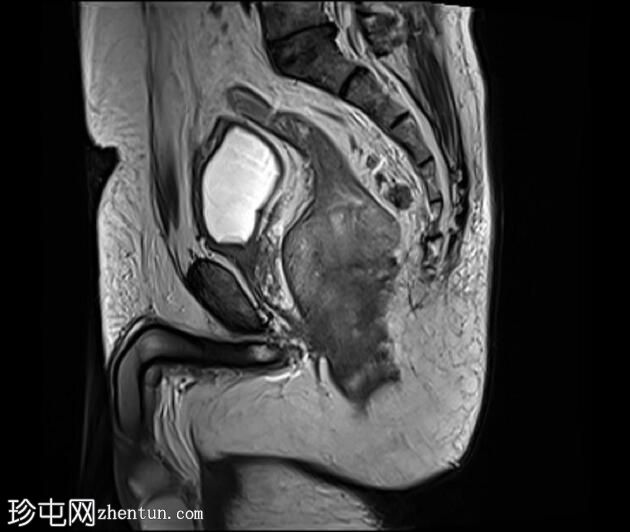

矢状位

6.jpeg

T2加权像

可见一不规则分叶状肿块,累及直肠中段和远端,头尾方向长约7 cm,下缘距肛缘约2.5 cm。在T1加权像和T2加权像上,该病灶相对于骨骼肌均呈高信号。 PDFS(脂肪抑制)图像显示持续高信号强度,提示存在黑色素和/或出血成分。

增强扫描显示病灶内呈不均匀强化。直肠下段7点钟位置的系膜筋膜受累。后方系膜可见少量淋巴结。未见邻近器官侵犯。